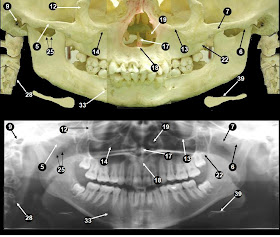

Panoramic X Ray Anatomical Landmarks - These Normal Radiographical Anatomical Landmarks Are Unique To Each Area Of The Maxilla Or Mandible And Appear Either Radiopaque Or Radiolucent.

Anatomical structures facilitates diagnosis and registration of dental records.

This method is useful in providing diagnostic information regarding identifiable landmarks because of a lack of three dimensional viewing, panoramic view provides limited information regarding anatomical limitations. Landmarks were selected to be clinically meaningful and clearly identifiable in 3d; Of reference anatomical landmarks in order to achieve accurate and undistorted panoramic. Automatic segmentation of mandible in. I was asked by representatives from panoramic corporation. Anatomical structures facilitates diagnosis and registration of dental records. Landmarks common to both the maxillary and mandibular radiographs.

External auditory meatus (external acoustic meatus). It is important to understand the landmarks normally seen on panoramic images in order to prevent misdiagnosis of a radiopaque or radiolucent area. Landmarks common to both the maxillary and mandibular radiographs. Panoramic radiography is a form of tomography; New and refurbished panoramic dental x ray machines for sale, including panoramic xray, panorex machine or panoramic x ray machine for sale at low prices. ๐Ÿ‘‰ enumerate all radiolucent landmarks visible on a panoramic radiograph. This study presents a fast and. 39 companies | 109 products. This method is useful in providing diagnostic information regarding identifiable landmarks because of a lack of three dimensional viewing, panoramic view provides limited information regarding anatomical limitations. The maxillary and mandibular anatomical structures such as pterygomaxillary fissure, incisive foramen mandibular canal, anterior loop of mental nerve and mental foramen were analysed. Automatic segmentation of mandible in. Of reference anatomical landmarks in order to achieve accurate and undistorted panoramic. I was asked by representatives from panoramic corporation. Accurate method for automatic segmentation of mandible in. Anatomical structures facilitates diagnosis and registration of dental records. Bony landmarks of the maxilla and surrounding structures: Anatomical landmarks (panoramic) learn by taking a quiz. This radiopaque landmark is only seen on a panoramic radiograph and is just anterior to the mandibular foramen. 0 ratings0% found this document useful (0 votes). * prior to any kind of surgery in the maxillofacial region, opgs are made to assess the anatomical location of various clinically important structures. Cephalometric analysis is an essential clinical and research tool in orthodontics for the orthodontic analysis and treatment planning. Learn vocabulary, terms and more with flashcards, games and other study tools. Dental panoramic x ray landmarks. Genial tubercles the genial tubercles are small bony spines found on the 35. Start studying panoramic normal anatomical landmarks. Thus, images of multiple planes are taken to make up the composite panoramic image. External auditory meatus (external acoustic meatus). Landmarks were selected to be clinically meaningful and clearly identifiable in 3d; Savesave anatomical landmarks of panoramic radiographs for later. Visibility of mandibular anatomical landmarks in panoramic radiography: Orthopantomogram procedure, uses and costs.